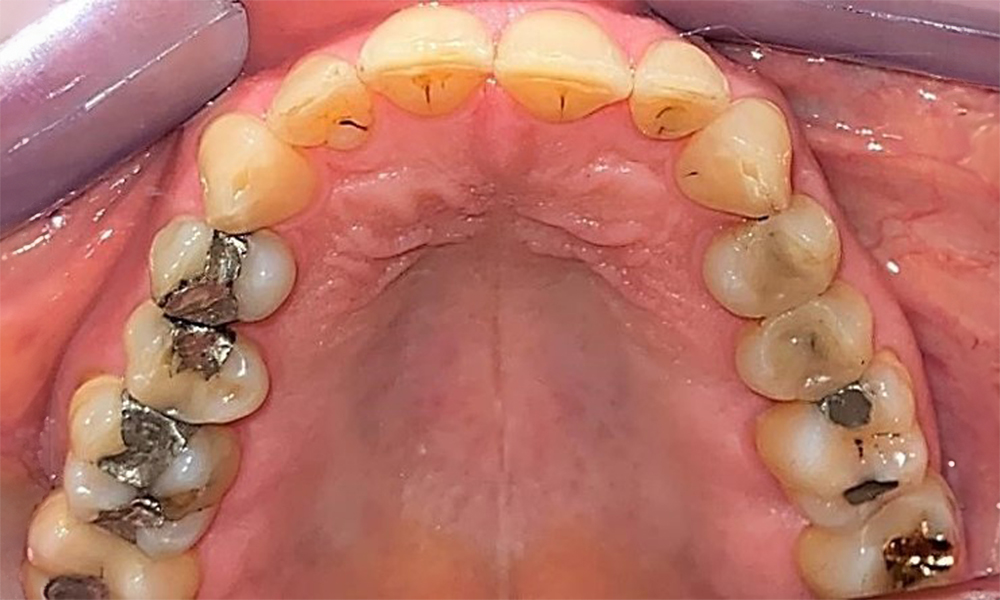

Occlusal view of the maxilla. Insufficient amalgam filling of 14 with a marginal gap.

Fig. 5 Occlusal view of the maxilla. Insufficient amalgam filling of 14 with a marginal gap. © Dr R. Krapf